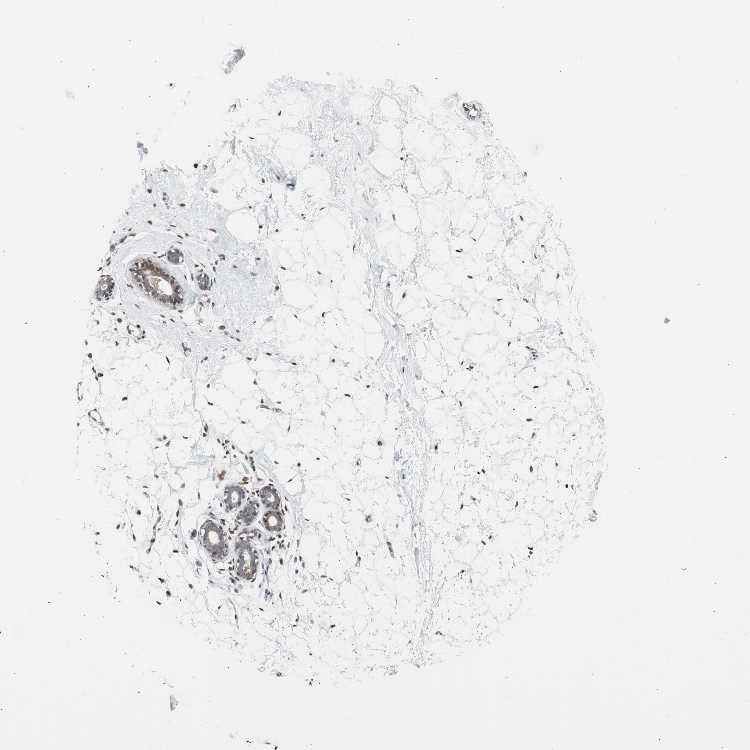

BREAST - Antibody stainingi

Antibody staining in the annotated cell types in the current human tissue is reported as not detected, low, medium, or high, based on conventional immunohistochemistry profiling in selected tissues. This score is based on the combination of the staining intensity and fraction of stained cells.

Each image is clickable and will lead to virtual microscopy that enables deeper exploration of all samples and also displays staining intensity scores, fraction scores and subcellular localization as well as patient and tissue information for each sample.

Antibody CAB004565Antibody CAB005352

Adipocytes HighMedium

Glandular cells HighMedium

Myoepithelial cells HighLow